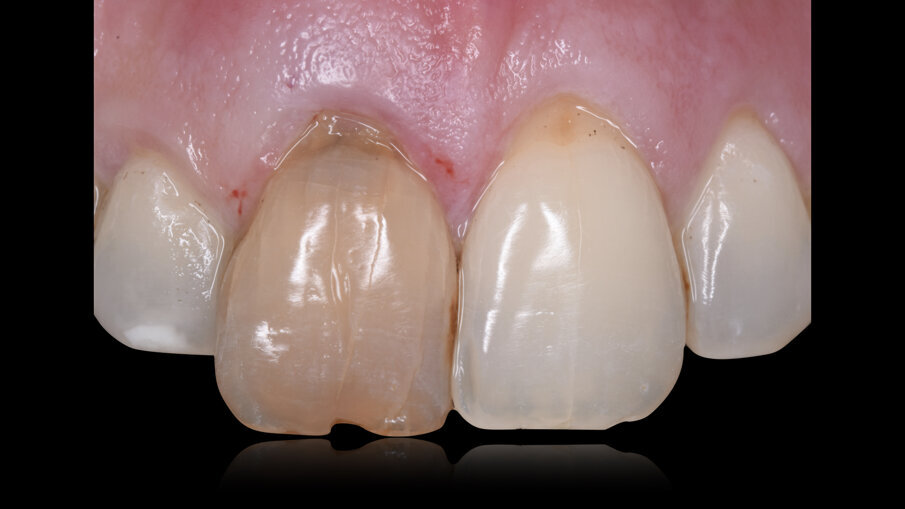

A distanza di 4 mesi dalla chirurgia implantare abbiamo ottenuto sul piano frontale un ottimo livellamento delle parabole gengivali con il ripristino di un’anatomia corretta e ideale sia dei margini gengivali di 1.1 e 2.1 sia delle papille interdentali mesiali e distali alla corona sull’impianto dell’1.1 (Fig. 15), mentre la rimozione del provvisorio avvitato ha permesso di evidenziare sul piano trasversale il condizionamento dei tessuti molli, la perfetta integrazione della matrice Fibro-Gide (Geistlich Pharma AG, Wolhusen, Switzerland) e la vascolarizzazione del sito con fibre circonferenziali ripristinando la corretta ideale anatomia attorno a un corona su impianto dal centro verso la periferia con epitelio connettivale, epitelio giunzione e epitelio sulculare (Figg. 16, 17); il nuovo livello di frequenza di risonanza è salito fino a 81 ISQ.

Dopo una prova estetica del colore e della tessitura superficiale, e un controllo radiografico bidimensionale, il caso è stato finalizzato posizionando il restauro in ceramica avvitato che è stato serrato con torque di 25 N /cm (Fig. 19). Si è ottenuto un mimetismo ideale e completamente naturale sia per quanto riguarda la componente bianca del restauro (ceramica) sia per la componente rosa (profilo, spessore e anatomia dei tessuti molli) risultando in un’estetica eccellente (Figg. 20-24).